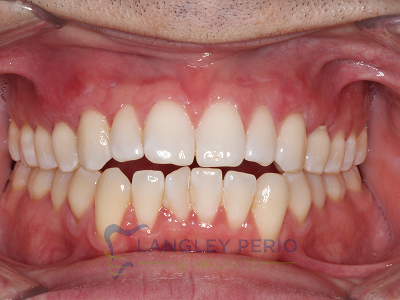

Case 1

Connective tissue grafting was performed to correct gingival clefting caused by over-aggressive toothbrushing